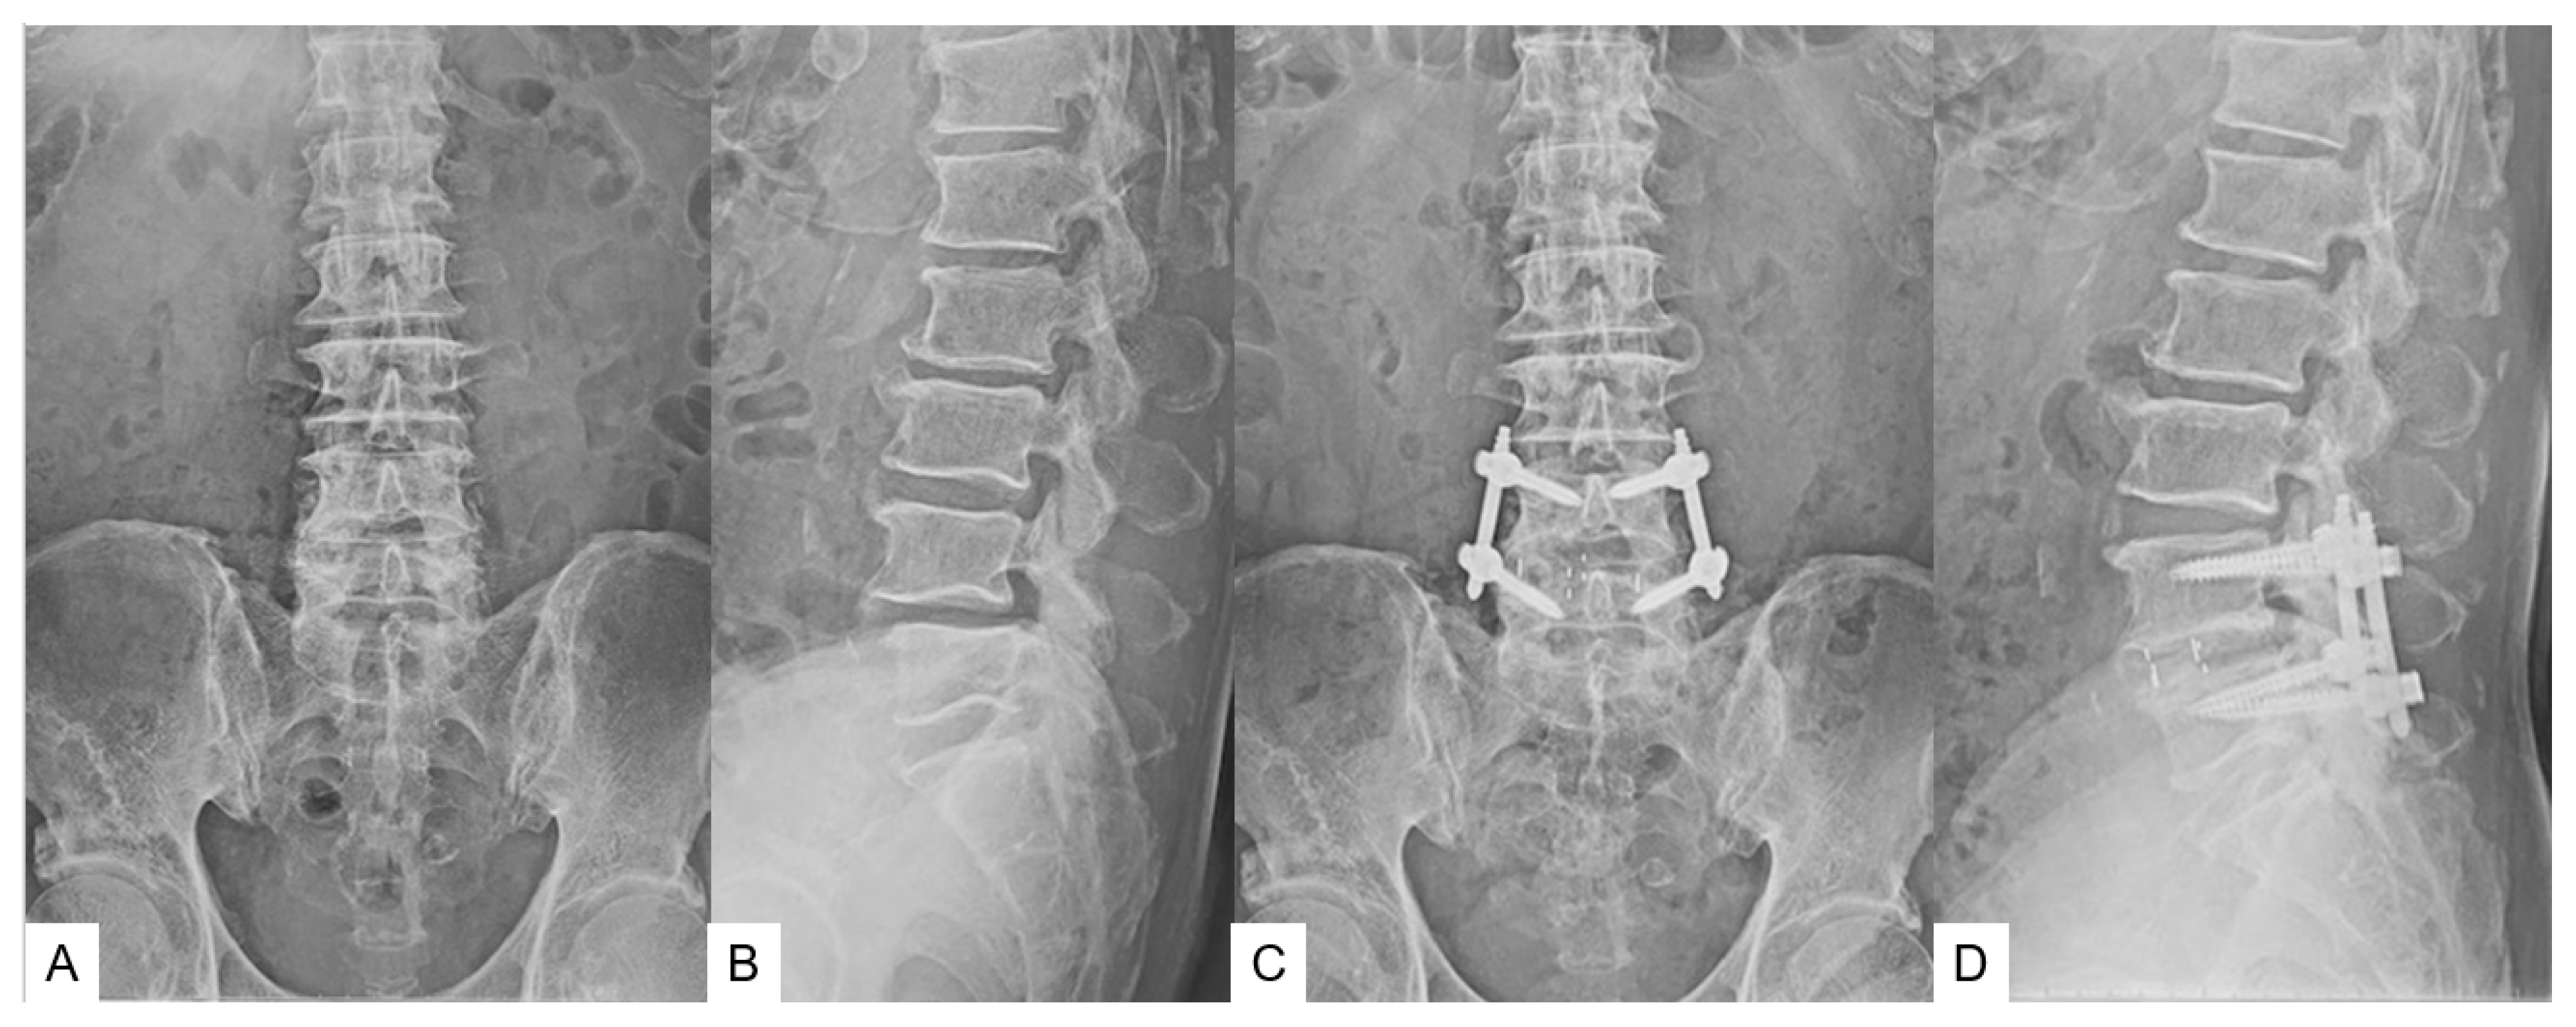

- Case 1 75-year-old man, L4 degenerative spondylolisthesis